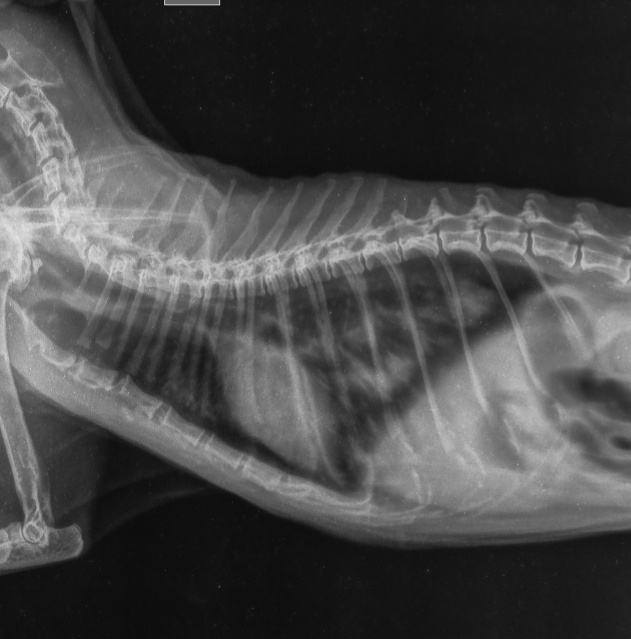

3. Рентгенография грудной клетки.

Проводится после стабилизации состояния. На снимке видно поджатое легкое, отставшее от грудной стенки, и скопление воздуха. Рентген также позволяет выявить сопутствующие травмы — переломы ребер, ушиб легкого, наличие жидкости (крови) в плевральной полости.